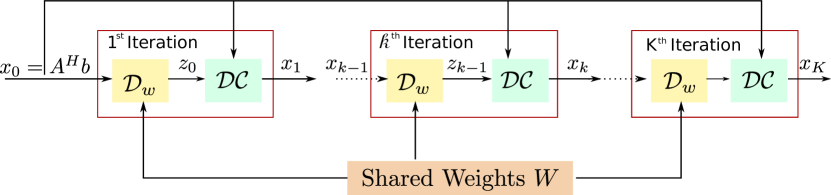

The algorithm is initialized with . The outline of the iterative framework is shown in Fig. LABEL:sub@subfig:mainarch. Once the number of iterations is fixed, the update rules can be viewed as an unrolled deep linear CNN, as shown in Fig. 1(c), whose weights at different iterations are shared. The proposed unrolled architecture has similarities to [18, 19, 16]. However, unlike these works, we use the same denoising operator at each iteration. Similarly, we use the same trainable regularization parameter at each iteration for consistency with (10a) & (10b). [18] and [19], (5). The key benefit of the proposed scheme is the quite significant reduction in the number of network parameters. Specifically, the number of parameters is smaller by a factor of the number of iterations. Our experiments demonstrate the improvement in the robustness of the training procedure and the improved quality of the reconstructions.

The CNN architecture used in this work is shown in Fig. 1(a). We used layer model with 64 filters at each layer to implement the block. Each layer consists of convolution (conv) followed by batch normalization (BN) [41] and a non-linear activation function ReLU (rectified linear unit, ). The -layer does not have ReLU to avoid truncating the negative part of the learned noise patterns. Following the residual learning strategy, the learned noise from block is added with the input of block to get the reconstructed image as the output of the block. The number of trainable parameters at each layer of the CNN network is shown in Table I. The output of block is fetched into data consistency (DC) layer as described in Fig. 1(b). The proposed recursive model, shown in Fig. 1(b), was unrolled assuming iterations of the alternating strategy (10b) and implemented in TensorFlow. Specifically, we set the number of layers as and number of iterations as . Since MR images are complex, the data consistency (DC) layer explicitly works with complex inputs and returns a complex output. The CNN part handles complex data by concatenating the real and imaginary part as channels i.e. we convert from space into space.

We use a two-step approach to initialize the network for training. We first trained a model for only one iteration, initializing the parameters with random values. This training is considerably faster than training the entire network. Since we use a recursive network with the same weights across iterations, the weights of the unrolled network at each iteration in Fig. 1(c) are initialized using the weights learned from the single iteration model. We observe that this two-step training strategy is considerably faster and reliable than initializing the full network using random weights. Since we use the same weights across iterations, we may choose the number of iterations in the reconstruction algorithm to be different from the ones assumed during training. The source code for the proposed MoDL scheme can be downloaded from this link: https://github.com/hkaggarwal/modl